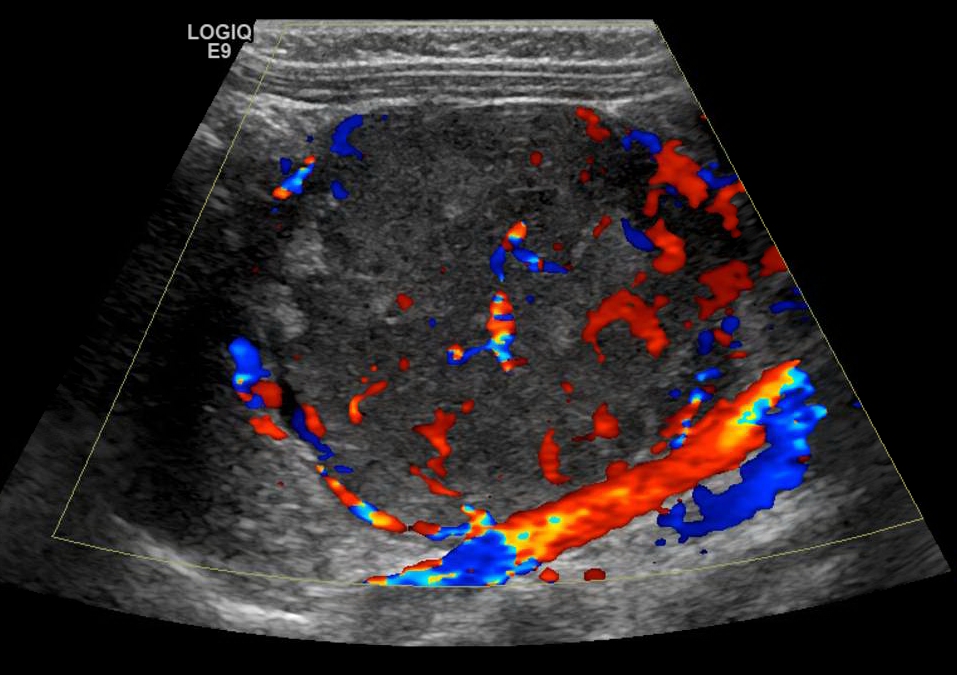

Ultrasound appearance

On ultrasound you may encounter a round or ovoid mass with mixed echogenicity often time does the punctate echogenic foci representing classifications.

Retroperitoneal Neuroblastoma